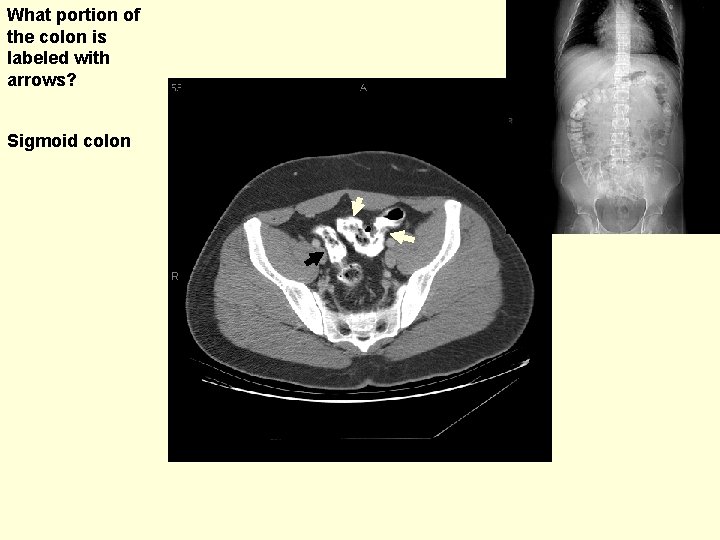

What portion of the colon is labeled with arrows? Sigmoid colon